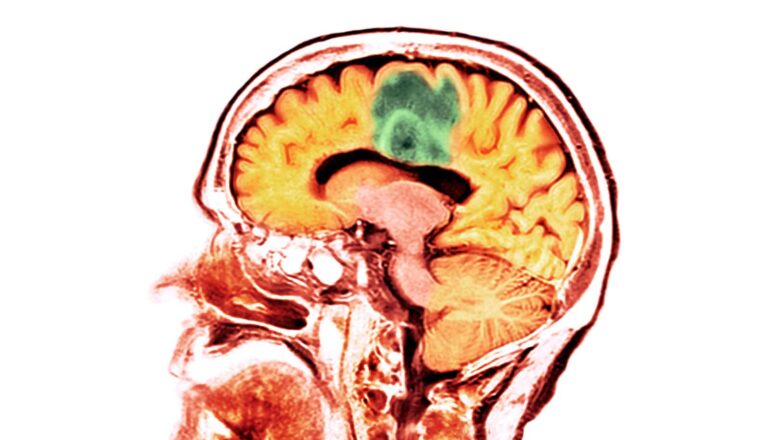

A new study reveals that adults who have suffered a moderate to severe traumatic brain injury are more likely to develop brain cancer.

Zafonte’s team examined more than 150-thousand civilian adults across three health systems, making this the largest and most varied study to date looking at a possible connection between brain tumor development and a history of TBI. They found that while patients with a mild TBI were not associated with a greater risk for brain cancer, patients who suffered a moderate to severe TBI were 50% more likely to develop a malignant brain tumor.

“Why moderate-to-severe TBIs increase the risk of tumors is not well-understood,” Zafonte says. “This could be because of disruptions in metabolic processes or an increase in inflammatory responses in the brain and nervous system.”

These findings may present an opportunity to identify brain tumors earlier. Patients with a medical history of a TBI could be screened for tumor growth, and the early detection of cancer would make it much more treatable and consequently improve patient outcomes. The study did not distinguish between different types of malignant brain tumors, though, and presents a research opportunity to see if there is a specific type linked to TBIs.